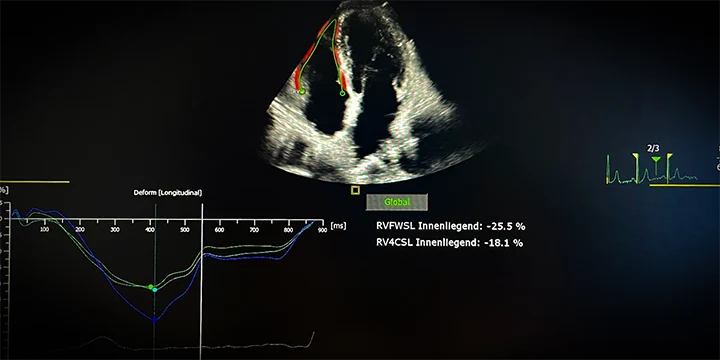

Strain-Analyse (Deformationsanalyse)

Die Strain-Analyse misst die Dehnbarkeit des Herzmuskels – also, wie gut sich das Herz bei jedem Schlag zusammenzieht. Mit modernster Speckle-Tracking-Technologie analysieren wir feinste Bewegungsmuster des Herzmuskels in Echtzeit. So können wir bereits frühzeitig Funktionsstörungen erkennen, bevor sie in anderen Messwerten sichtbar werden.

Typische Einsatzgebiete sind:

- Verlaufskontrollen bei Chemotherapie (kardioonkologische Überwachung)

- Früherkennung bei Amyloidose, Bluthochdruck oder Diabetes

- Beurteilung der Funktion von linker Herzkammer (GLS), linkem Vorhof (LA-Strain) und rechtem Ventrikel (RV-Strain)